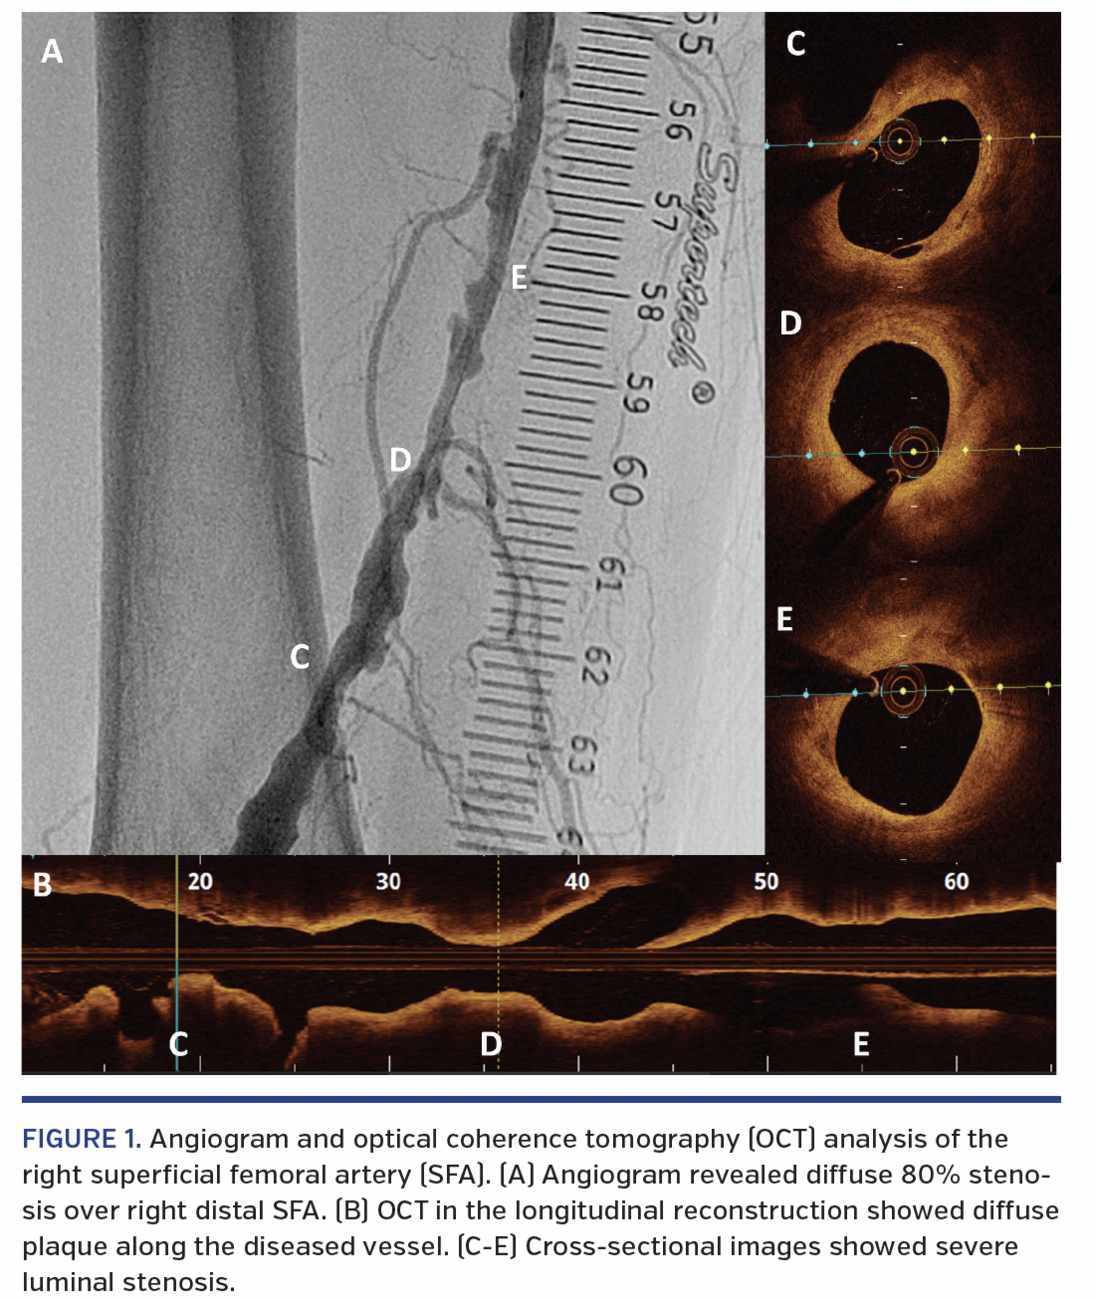

A 70-year-old man presented with lifestyle-limiting intermittent claudication (Rutherford stage III) affecting the right lower extremity. Physical examination of the right lower limb revealed weak distal pulses and a diminished ankle-brachial index of 0.6. Peripheral angiogram showed diffuse 80% stenosis over the right distal superficial femoral artery (SFA).

The HawkOne directional atherectomy system (Medtronic Peripheral) was used to restore blood flow by removing plaque. After placing a 7 mm SpiderFX device (Medtronic Peripheral), optical coherence tomography (OCT) was acquired to assess baseline plaque load (Figure 1). Several runs of directional atherectomy were done. Angiogram and OCT were then obtained to assess the result of directional atherectomy (Figure 2). Drug-eluting balloon was applied afterward. The final angiographic result was excellent. A 3-month course of dual-antiplatelet therapy was given, followed by lifelong aspirin. There was no recurrence of symptoms at subsequent 1-year follow-up.